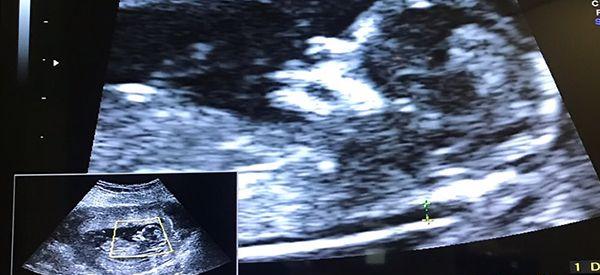

怀孕12周,刚去做了nt检查,今天刚拿到报告单,看了下结果,在正常值范围内,但是听别的宝妈说孕12周的nt能暗示男女,而且准确率高达90,我有点好奇,也想知道自己怀的是男孩女孩,所以想知道nt单看男女是怎么看的?

事实上,nt检查主要是了解胎儿的健康状况的,用来排出是否有先天性神经管畸形的风险,并没有判断胎儿性别的作用,但不少孕妈妈仍然会从nt数据来判断宝宝男女,下面就来了解一下具体是怎么看的吧。

报告单上有nt图象和nt值

2、通过nt图看男女

主要是看胎儿的姿势,如果nt图是弯着的一般都是男孩,平行的话一般都是女孩;另外,还可以看胎儿的脊柱线那里,如果是大于30度的话,男孩几率大,小于30度的话女孩几率大。